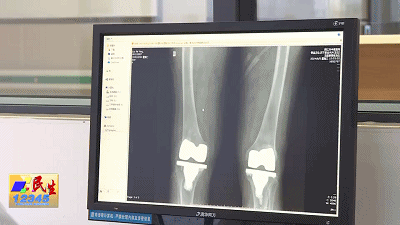

原来早在16年前,患者刘奶奶因双膝重度骨关节炎前往市中中医院骨关节科进行了双膝关节置换手术。因当时刘奶奶已有77岁的年纪,由医院骨关节科张帅主任亲自操刀手术,加上刘奶奶算是阳江地区较早开展人工膝关节置换术的一批患者,因此医院对于刘奶奶的再次就诊印象深刻。

而这次刘奶奶与医院的“重逢”,则是因其不慎摔倒造成髋关节骨折。经过详细检查,张帅主任再次为刘奶奶开展了右侧人工股骨头置换术,术后第二天她就能下地扶助行器行走。

医生表示,这几年随着医学技术的提高、医疗器械的优化,关节置换术有了肉眼可见的进步。不仅表现在手术治疗越来越成熟,治疗时间大大缩短了,为患者所安装的假体性能也越来越好。

林医生还告诉记者,关节置换术使用的人工假体并没有具体的使用年限,假体均是贴合患者情况“量身定制”,只要患者生活习惯后,不过分负重活动,跟正常人生活是一样的,因此使用年限需因人而异。